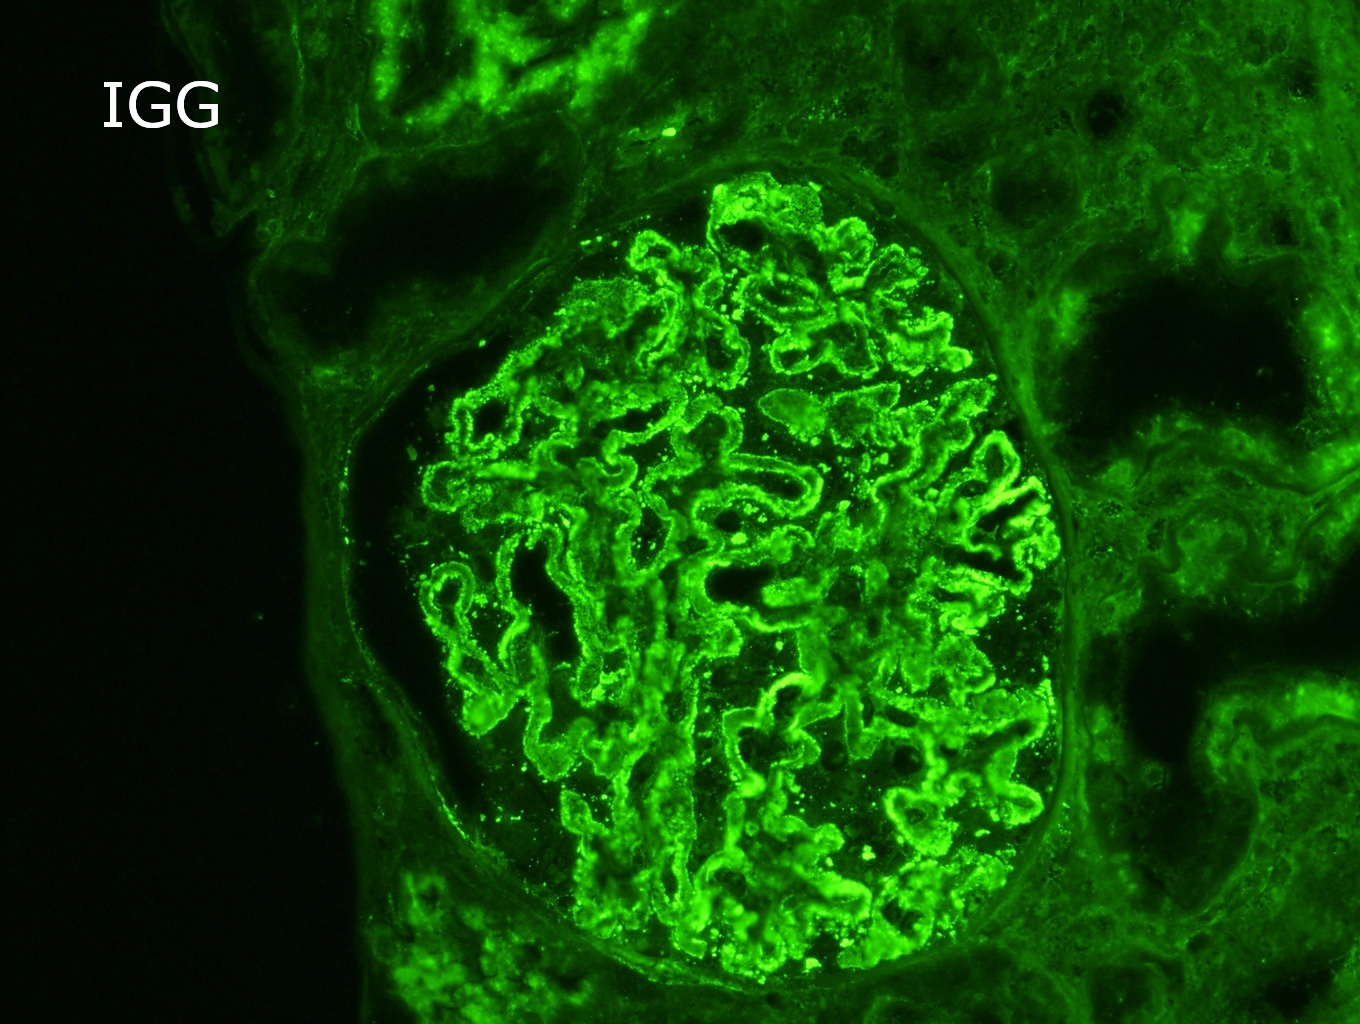

Immunofluorescence description

- Finely granular staining for IgG, predominately IgG4, presents uniformly in a subepithelial distribution in all glomeruli (Colvin: Diagnostic Pathology - Kidney Diseases, 2nd Edition, 2015, Zhou: Silva's Diagnostic Renal Pathology, 2nd Edition, 2017)

Immunofluorescence images

- Immunofluorescence microscopy:

- Number of glomeruli: 4

- Diffuse granular staining of the glomerular basement membrane for IgG (+++) and C3 (++); there were no deposits of IgA, IgM, C1q or fibrin.